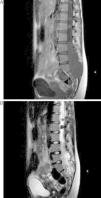

El meningioma de células claras es una variedad infrecuente de meningioma. Se describe el caso de un meningioma espinal multifocal de células claras presente en una paciente de 20 años de edad. Clínicamente refiere lumbalgia de aproximadamente 2 años de evolución. En el estudio de resonancia magnética nuclear (RMN) se evidencia gran tumoración lumbosacra, que ocupa el canal raquídeo de L4 a S2, asociada a 2 lesiones satélites en la región lumbar. Una tumoración intra-extradural fue resecada quirúrgicamente, confirmándose el diagnóstico anatomopatológico de meningioma de células claras. Se resecan así mismo ambas lesiones satélites con idéntico diagnóstico histológico.

Clear cell meningioma is a rare morphological form of meningioma. This case report describes a very rare case of multifocal clear cell meningioma in the sacral and lumbar spine. The patient was a 20-year-old female who presented back pain. Magnetic resonance imaging (MRI) revealed a large tumour at L4 to S2 level associated with two, smaller, satellite tumours at the lumbar level. An intra-extradural tumour was surgically removed and the pathological diagnosis of clear cell meningioma was confirmed. Both satellite lesions were also resected and their histopathological diagnosis was the same.